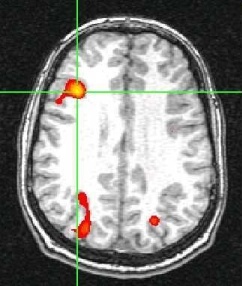

FMRI is a method of measuring the flow of oxygenated blood in the brain (Ogawa et al., 1990A, 1990B; Bandettini, 1992). FMRI is based on the BOLD effect where BOLD stands for blood oxygen-level dependent. BOLD MRI is accomplished by first exposing a patient or volunteer to a stimulus or having them engage in a cognitive activity while acquiring single-shot images of their brain. The region of the brain that is responding to the stimulus or is engaged in the activity will experience an increase in metabolism. This metabolic increase will require additional oxygen. Therefore, there will be an increase in oxygenated blood flow (oxyhemoglobin) to the local brain area that is active. Oxyhemoglobin differs in it’s magnetic properties from deoxyhemoglobin. Oxyhemoglobin is diamagnetic like water and cellular tissue. Deoxyhemoglobin is more paramagnetic than tissue so it produces a stronger MR interaction. We take advantage of these differences between oxy and deoxyhemoglobin in BOLD imaging by acquiring images during an “active” state (more oxyhemoglobin) and in a “resting” state (more deoxyhemoglobin). We see a signal increase in the “active” state and a signal decrease in the resting state. Again, these signal changes are due to the different magnetic properties of oxy- and deoxyhemoglobin. The figure below shows a typical BOLD time course (shown in black) where there are 4 “active” states and 4 “resting” states. With prior knowledge of the activation timing (shown in red), we can perform a statistical test on the data to determine which areas of the brain are active. We then overlay this statistical map (shown in color) on a high resolution MR image so that one can visualize the functional information in relation to relevant anatomical landmarks.